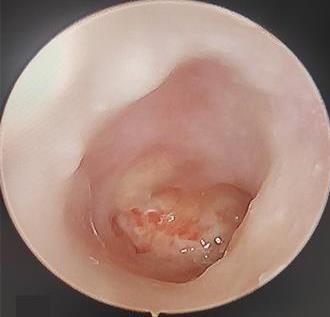

• 色素内镜和窄带成像技术联合放大内镜对早期结直肠癌及癌前病变的诊断价值研究

摘要:目的 探究色素内镜(CE)和窄带成像技术(NBI)联合放大内镜(ME)对早期结直肠癌及癌前病变的诊断价值研究。方法 选取2023年8月-2024年7月于该院接受检查的疑似早期结直肠癌及癌前病变的患者160例。采用四格表法,分析NBI-ME和CE-ME检测早期结直肠癌及癌前病变的敏感度、特异度和准确度;采用Kappa一致性检验,分析CE-ME和NBI-ME诊断早期结直肠癌及癌前病变与病理检查的一致性。结果 病理结果显示,良性病变52例,癌前病变90例,结直肠癌18例。CE-ME检测结果显示,良性病变43例,癌前病变101例,结直肠癌16例,漏诊率为33.33%;CE-ME诊断早期结直肠癌及癌前病变与病理检查的一致性中度(Kappa = 0.605,P < 0.01),敏感度为66.67%,特异度为97.18%,准确度为93.75%。NBI-ME检查结果显示,良性病变43例,癌前病变100例,结直肠癌17例,漏诊率为16.67%,NBI-ME诊断早期结直肠癌及癌前病变与病理检查的一致性较高(Kappa = 0.714,P < 0.01),敏感度为88.33%,特异度为98.59%,准确度为96.88%。CE-ME与NBI-ME两者联合检查结果显示,良性病变56例,癌前病变86例,结直肠癌18例,漏诊率为5.56%,两者联合诊断早期结直肠癌及癌前病变与病理检查的一致性极高(Kappa = 0.857,P < 0.01),敏感度为94.44%,特异度为99.30%,准确度为98.75%,高于CE-ME和NBI-ME单独检查。结论 CE和NBI联合ME对早期结直肠癌及癌前病变具有较高的诊断价值。值得应用于临床。